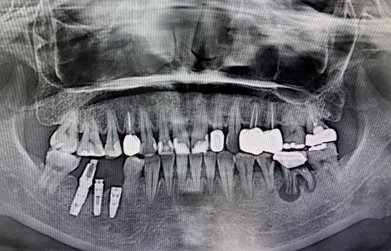

一口潔白整齊的牙齒,可以增加你的自信,讓你盡情展露笑容。但是很多人因?yàn)楦鞣N原因,從而缺失了自己的牙齒。嚴(yán)重影響的形象美觀及正常咀嚼功能。不過現(xiàn)在種植牙是非常熱門的項(xiàng)目,效果也是很不錯(cuò)的。 種植